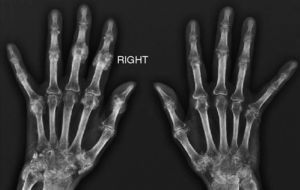

We present the case of a 63-year-old housewife who had a history of type 2 diabetes, hypertension and dyslipidemia, with good control, for which she was taking metformin, enalapril and atorvastatin. There was nothing notable in her family history, she did not consume harmful substances and was not contact with animals. She was referred to us with a 2-year history of polyarthralgia at irregular intervals, with predominantly mechanical symptoms, in small joints of the hands and feet. There was no swelling, but she reported having morning stiffness in the hands that lasted approximately 2h. In the review of organ systems for her medical history, she mentioned the development of a dry cough and dyspnea on moderate exertion since the onset of the arthralgias, as well as the appearance of Raynaud's phenomenon in her hands, without vasculitic lesions, one year earlier. Her appetite and weight had not been affected and she had no fever. Physical examination showed that her general health was good, with resting eupnea and no evidence of adenopathy or skin lesions; auscultation of heart and lungs revealed Velcro crackles down to middle lung fields, but there were no other findings; on rheumatological examination, she was found to experience pain on flexion and extension of both wrists, without synovitis, and small, cold, painless, semi-indurated lesions at some metacarpophalangeal and interphalangeal joints of the hands (Fig. 1); in the rest of the joint areas, there was no pain, limitations of the range of movement or swelling. The results of the neurovascular examination were normal, with no pain in response to pressure on the limb musculature or functional disability. The laboratory findings were as follows: complete blood count, blood biochemistry, acute phase reactants, aldolase, creatine kinase, thyroid hormones and parathyroid hormone were within normal range; the autoimmunity study only revealed positivity for anti-hystidyl-tRNA synthetase antibodies (anti-Jo-1) at a high titer (rheumatoid factor and anti-cyclic citrullinated peptide, antinuclear, anti-U1-RNP, anti-Ro anti-cytoplasmic and anti-endomysium antibodies were all normal). The electromyographic study of upper and lower limbs detected no evidence of inflammatory myopathy. The imaging studies performed included: radiographies of elbows, hands (Fig. 2), pelvis, knees and feet. The only abnormal findings were calcium deposits in periarticular areas of the hands, together with osteopenia, with no evidence of erosion of any joint. High-resolution radiography and chest tomography revealed a reticular pattern compatible with interstitial pneumonia. Lung biopsy was performed, and the final diagnosis was usual fibrosing interstitial lung disease. On the basis of the clinical data and results of the supplemental tests performed, we established a diagnosis of antisynthetase syndrome.

With respect to the rheumatic manifestations of the antisynthetase syndrome, non-erosive symmetric polyarticular involvement is that most frequently found, and can be associated with distal calcinosis. Our patient reported no episodes of joint inflammation and we did not observe synovitis in our examination. Given that calcinosis usually develops in areas in which there has been an earlier inflammatory process, in our patient, the calcinosis may be the result of a previous subclinical inflammatory process (the patient was referred to us 2 years after the onset of her symptoms).

A recent publication from the Mayo Clinic4 dealt with the relationship between calcinosis and different connective tissue diseases. The rheumatic disease most frequently associated with calcinosis was dermatomyositis, followed by systemic sclerosis, mixed connective tissue disease and systemic lupus erythematosus. Approximately between 3% and 5% of the cases of antisynthetase syndrome can be classified as syndromes that overlap with other connective tissue diseases such as rheumatoid arthritis, systemic lupus erythematosus, systemic sclerosis or Sjögren's syndrome.5 The clinical and analytical data, data on autoimmunity, imaging studies and neurophysiological study ruled out all of these connective tissue diseases, as well as an overlap syndrome involving rheumatoid arthritis, as the cause of the calcinosis observed in our patient. Another interesting aspect of our case is the finding of periarticular calcinosis only in the hands, despite the fact that when calcinosis is associated with connective tissue diseases, it usually affects the areas of joint extension of the extremities in the form of a multifocal condition. Other processes that can cause calcinosis, although they were ruled out in our patient, are metabolic diseases (chronic nephropathy, hyperparathyroidism and hypervitaminosis D), parasitic infections like cysticercosis, and processes involved in muscle injuries or even periarticular injections.

The interest in our case lies in the presentation of calcinosis localized exclusively in the hands, with no evidence of previous inflammatory activity in or around the joints, in an anti-Jo-1-positive patient with antisynthetase syndrome, with no muscle involvement.